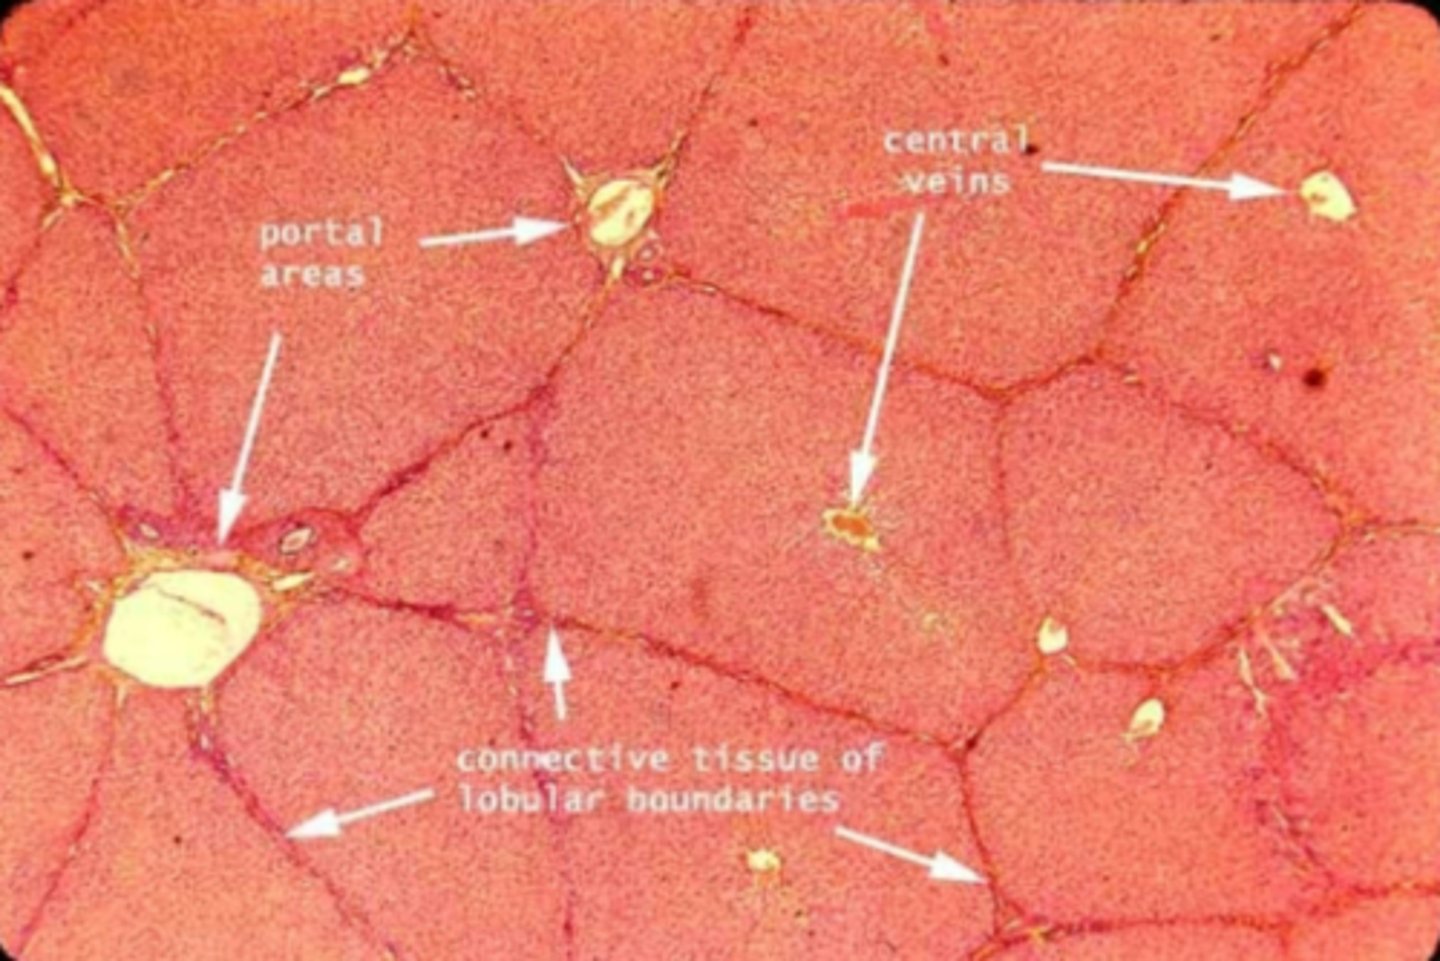

Liver

What is this?